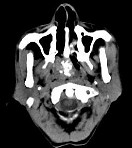

- 多项选择题男性,57岁, 睡觉打鼾,近来加重, CT扫描如图所示,请选择正确的描述和答案  (    )

- A、鼻咽腔偏右侧可见类圆形软组织块影

- B、肿块内密度尚均匀,其上方见较多钙化影

- C、肿块边缘大部清楚,邻近结构未见明显受侵

- D、考虑为鼻咽癌

- E、考虑为鼻咽部多形性腺瘤